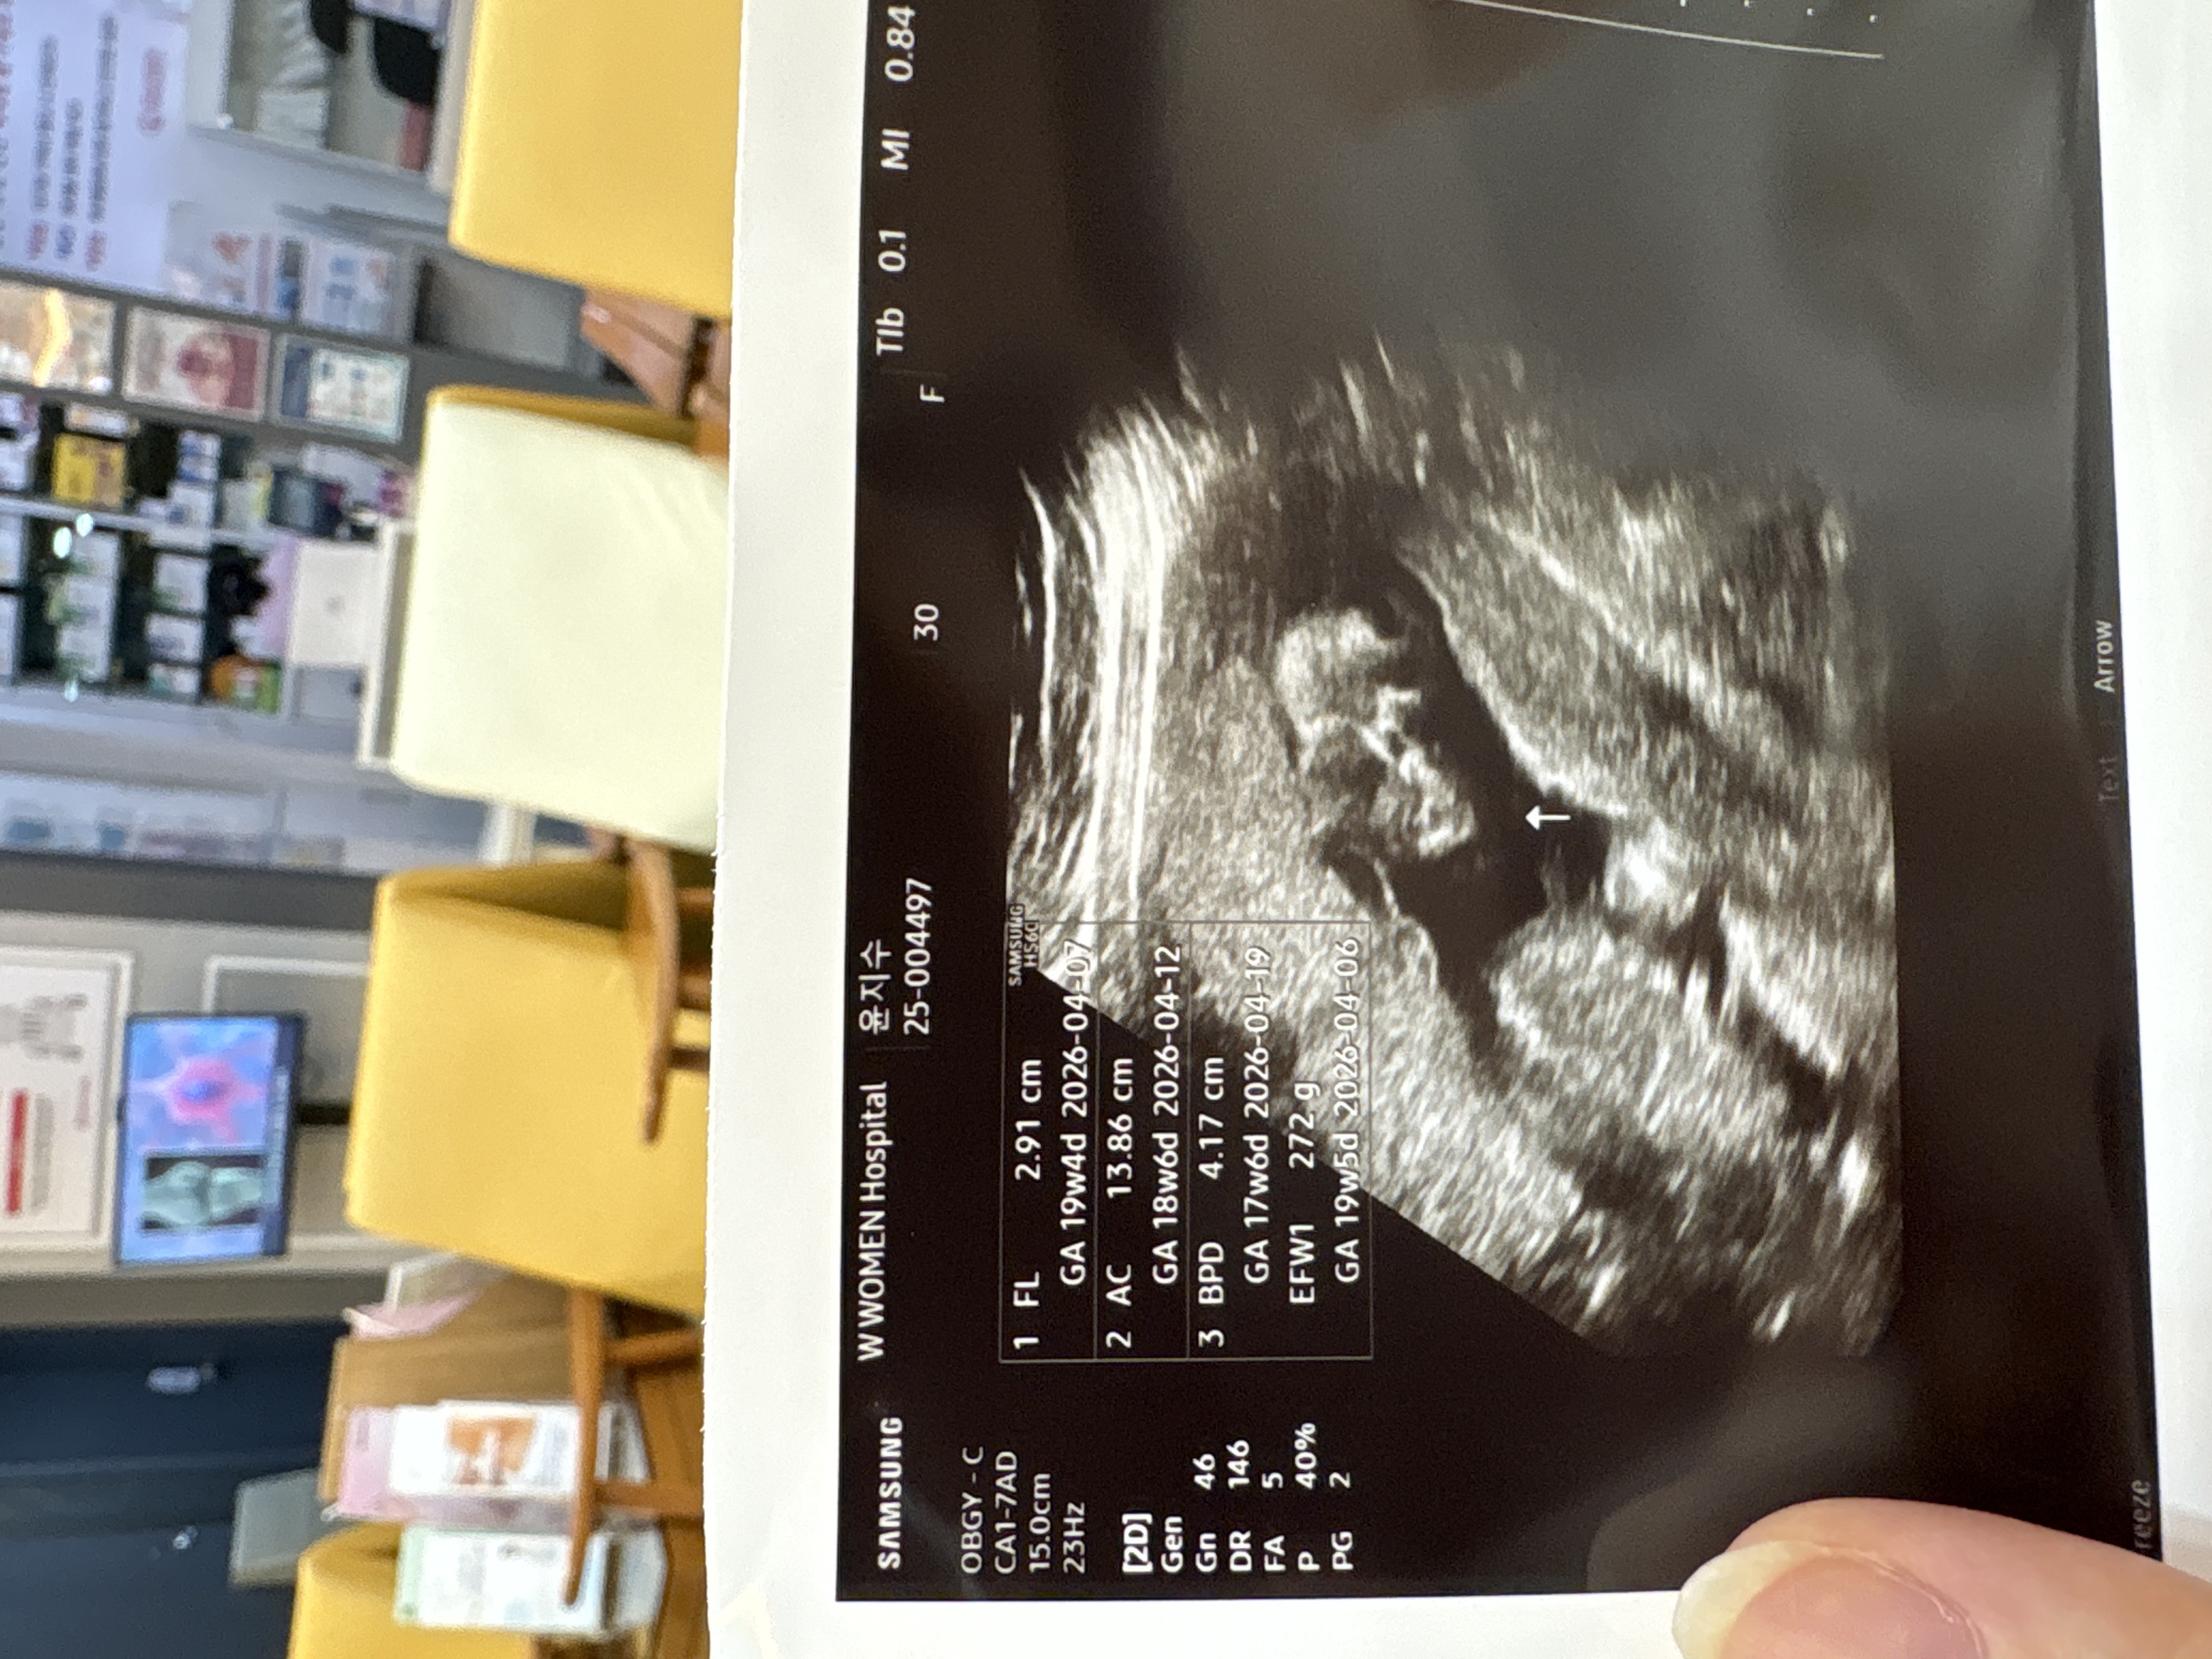

아기가 잘안큰대요..ㅜㅜ

20주1일차에 정기검진갔는데 16주에 갔을때도 아기가주수보다 좀 작다고했는데 이번에가니 여전히 작다구..ㅜㅜ잘좀먹으라고 혼났는데 마냥제가안먹어서가 아니고 태반문제나 아기가 문제일까봐 걱정되네요ㅠㅠ태반도 약간뻐끔?한부분들이 좀 보였어요..이러면아기한테 영양분이 제대로 안가보 있을수도 있다는거라더라고요 선생님이.일단한달동안많이먹고 다시보자는데 소화는안되지 입맛은없지 남편은 이것저것먹으라하는데 후 ㅠㅠ 저같으신분 있으셨을까요?

초음파 항목보면..다리길이나이런건 길구 머리랑 복부가 작은거에요! 딱히 큰 문제가 있다거 하신게 아니몬 서구형 체질이다 긍정적으로 생각해보세요 ㅎㅎ 저희애는...머리둘레랑 복부가 너무 커서 오히려 걱정인데요 뭐 ㅠㅠㅠ